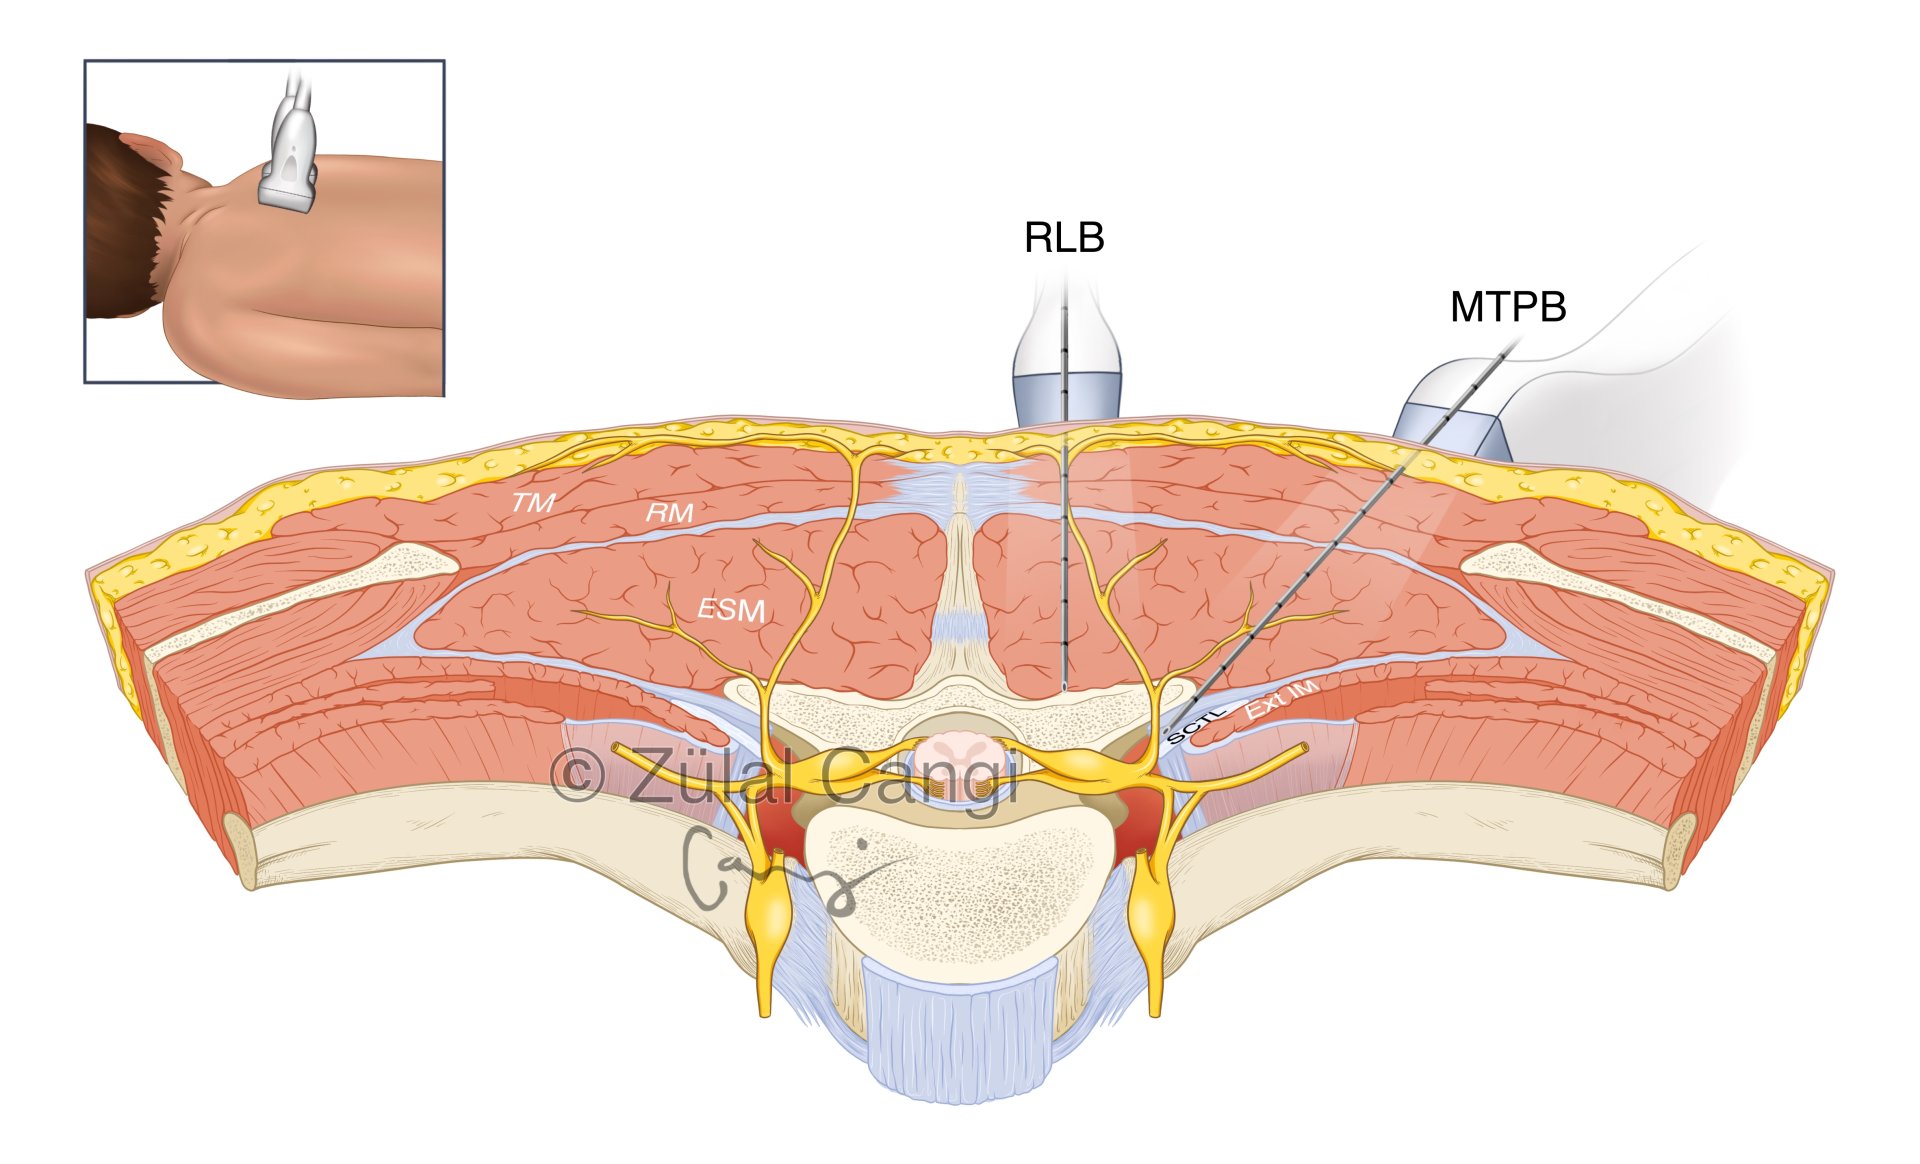

Sanatın estetiğini bilimin kesinliğiyle bir araya getiren Zülal Cangi, medikal ve bilimsel illüstrasyon alanındaki çalışmalarıyla akademik yayınlar, eğitim materyalleri ve çeşitli bilimsel platformlar için görsel içerikler üretmektedir. Amacı, bilimsel bilgiyi yalnızca doğru biçimde aktarmakla kalmayıp, aynı zamanda öğretici ve estetik bir dille görünür kılmaktır.

PORTFÖY